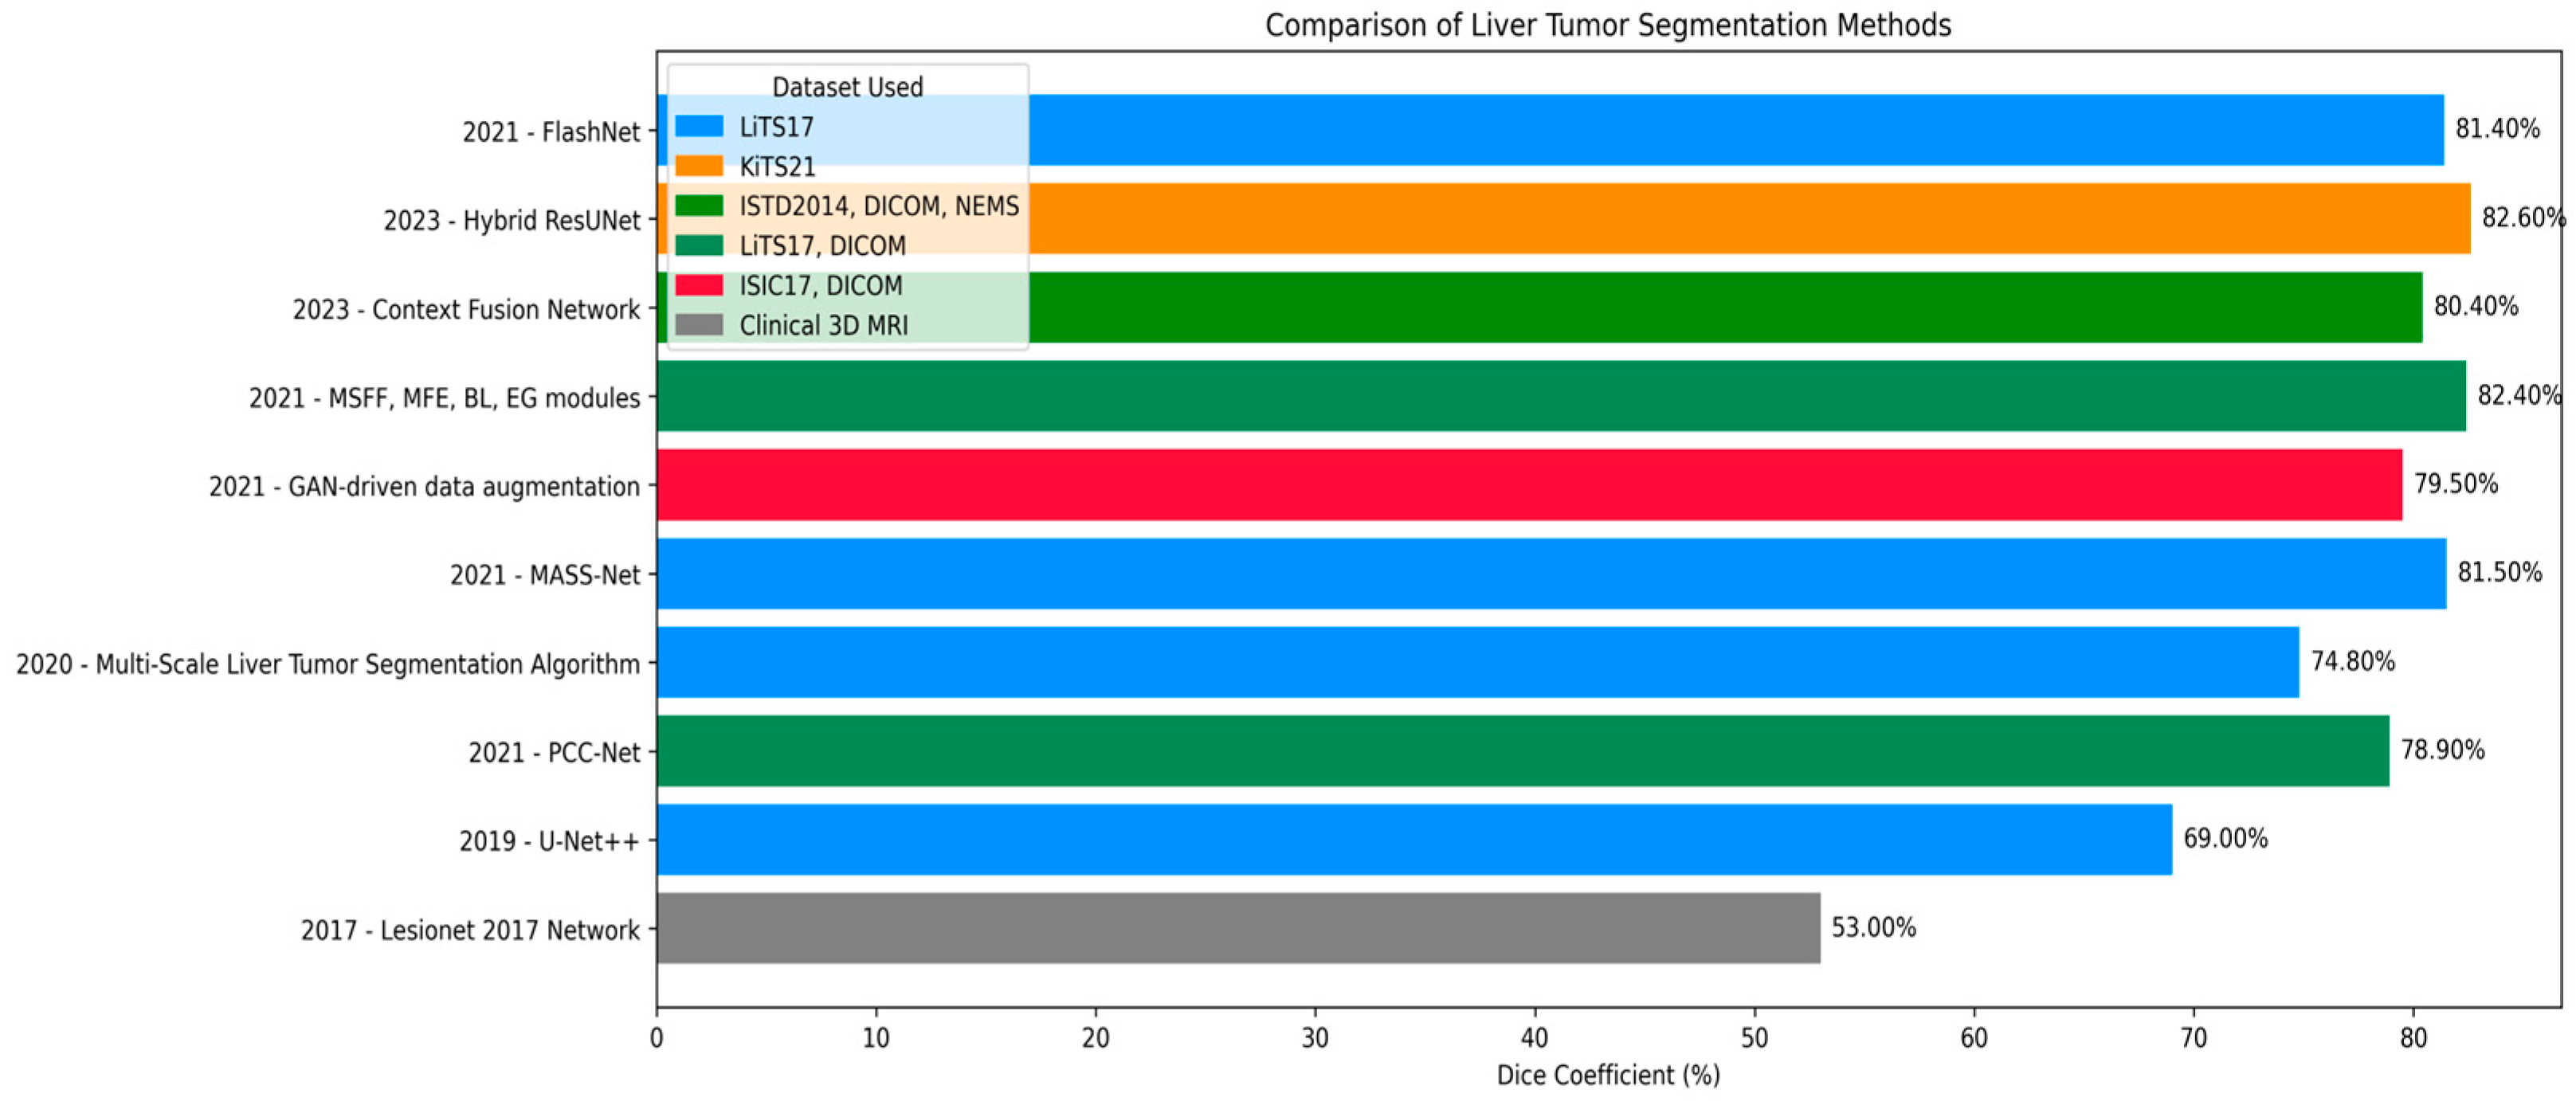

4.4. Comparison

4.5. Analysis Using Different Optimizers

| Ref | Technique | Dice Coefficient (%) | Jaccard Index (IoU) (%) |

|---|---|---|---|

| [30] | Multi-Scale Liver Tumor Segmentation Algorithm | 74.3 | – |

| [31] | PGC-Net | 73.63 | – |

| [34] | PAKS-Net | 76.9 | – |

| [33] | MSFF, MFF, EI, EG modules | 85.55 | 81.11 |

| [46] | GAN-driven data augmentation strategy | 60.5 | – |

| [35] | Context Fusion Network with TSA & MSA skip connections | 85.97 | 81.56 |

| [45] | Hybrid “FasNet” Model with Attention and Monte Carlo Dropout | 87.66 | 84.87 |

| Our proposed | LiTs-Res-Unet + WOA | 92.38 | 86.73 |